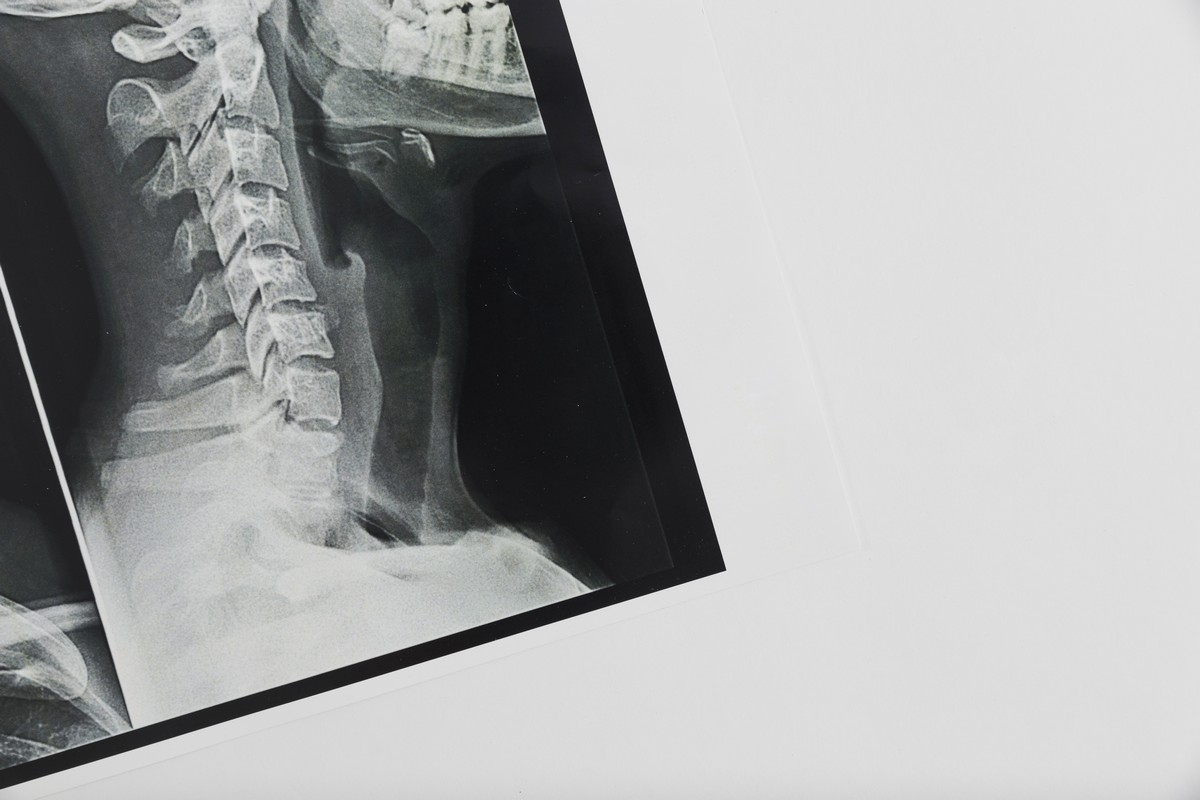

МРТ шейного отдела — информативный, неинвазивный метод визуализации, который позволяет с высокой точностью оценить состояние позвонков, межпозвоночных дисков, нервных корешков, связок, мягких тканей, сосудистых структур шеи.

Это томографическое исследование, основанное на воздействии магнитного поля и радиочастотных импульсов. Для этого метода не применяется рентген-излучение, поэтому он подходит для пациентов разного возраста, частого применения без риска накопленного облучения.

В процессе сканирования формируются послойные изображения анатомических структур, что помогает оценить состояние позвоночного канала, окружающих его тканей.

Исследование позволяет с высокой точностью визуализировать:

• состояние межпозвонковых дисков, включая протрузии, грыжи;

• высоту дисков, признаки дистрофии и дегенерации структур;

• сдавливание спинномозговых нервных корешков, тканей спинного мозга;

• стеноз позвоночного канала;

• воспаления, отеки мягких тканей;

• опухолевые процессы позвоночного столба, шейных отделов спинного мозга;

• последствия травм: микротрещины, смещения, подвывихи;

• состояние сосудистых структур, включая позвоночные артерии.